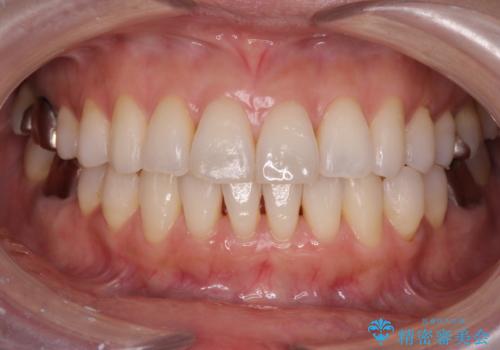

[ 非抜歯矯正 ] 歯を抜かずに出っ歯の治療

![[ 非抜歯矯正 ] 歯を抜かずに出っ歯の治療の症例 治療前](https://seimitsushinbi.jp/wp/wp-content/uploads/2025/03/IMG_6660-500x350.jpg?v=1741945892)

![[ 非抜歯矯正 ] 歯を抜かずに出っ歯の治療の症例 治療後](https://seimitsushinbi.jp/wp/wp-content/uploads/2025/03/IMG_7513-500x350.jpg?v=1741945816)